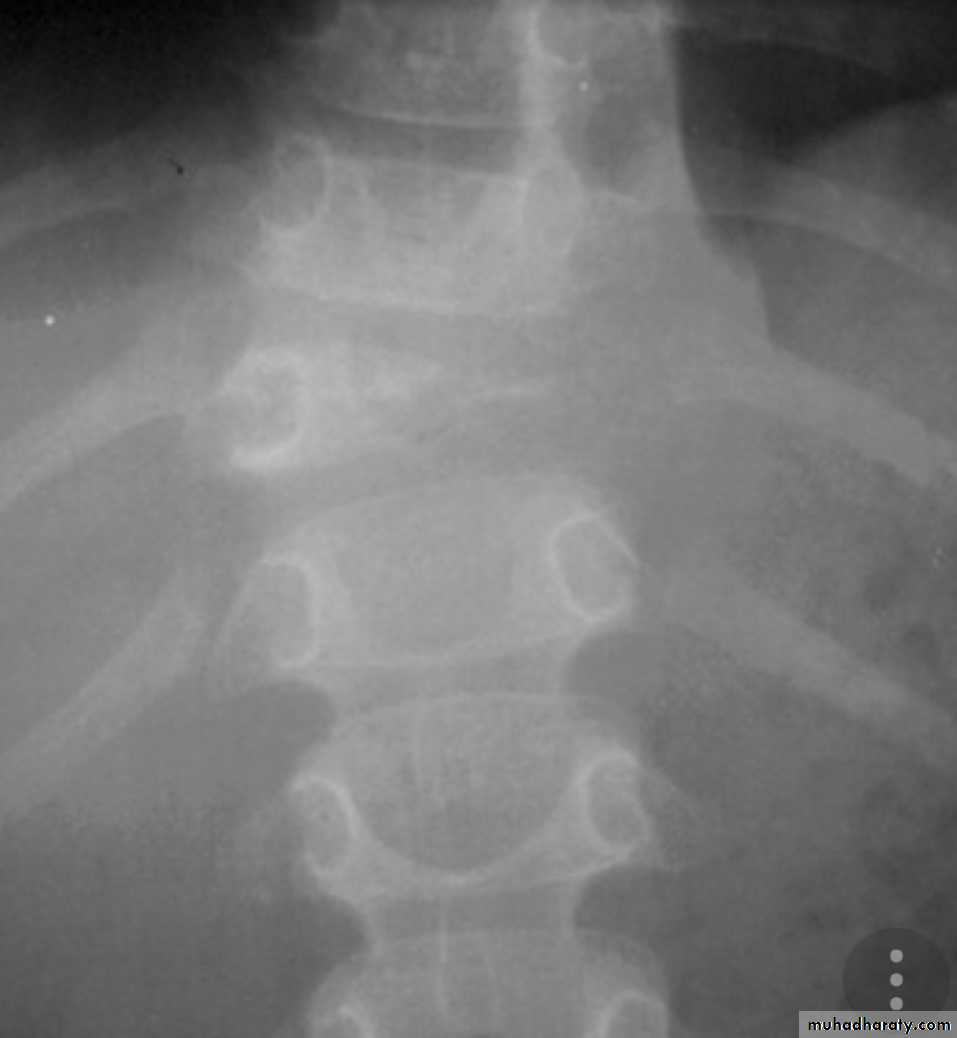

X- ray,